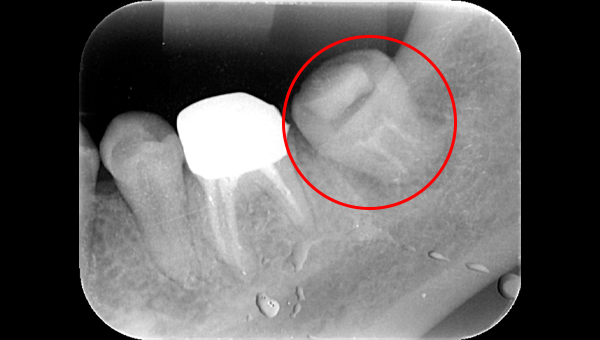

2022.7.9 経過観察後

口腔内写真

レントゲン写真

根管治療後3ヶ月です。根のまわりの骨がやや白くなってきているのがわかります。だんだん骨の添加がみられている証拠になります。

ここまで治癒していればかぶせ物をかぶせても問題ないと判断しました。